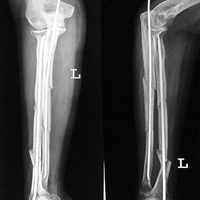

Case:8 Polytrauma

Patient having closed segmented fracture midshaft & lower 1/3 Tibia with closed fracture superior & inferior pubic rami right side with pelvis fracture following vehicular accident wastreated with intramedullary nail for fracture tibia and external fixator for fracture pelvis.

Immdiate Post-op

Post-op Lateral

Post-op 1 and half months follow-up

Post Uninon-3Months